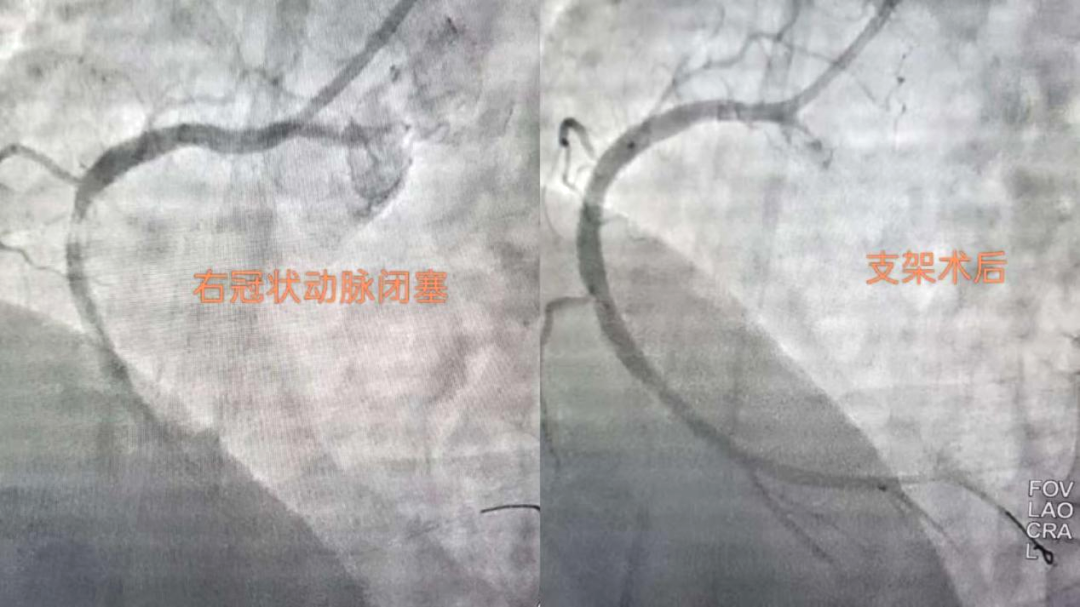

搶時間就是搶生命!06:46穿刺,06:47成功,06:49冠脈造影明確:右冠狀動脈中段完全閉塞。導(dǎo)絲迅速通過,支架精準(zhǔn)植入,07:03血流恢復(fù),手術(shù)成功結(jié)束?;颊咝赝疵黠@緩解,生命體征趨于平穩(wěn)。從入院到血管再通,不到兩小時。